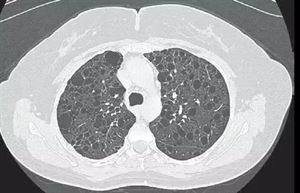

淋巴管肌瘤?。╨ymphangiomyomatosis,LAM)是一種比較罕見的疾病,幾乎所有的病例均發(fā)生于女性,以育齡期女性為主,平均年齡30~40歲。LAM主要累及肺臟,典型表現(xiàn)為彌漫性囊性改變,嚴(yán)重影響患者肺功能,而目前尚缺乏有效的治療方法。 2018年5月11日,國(guó)家衛(wèi)生健康委員會(huì)等5部門聯(lián)合制定了《第一批罕見病目錄》,淋巴管肌瘤病被收錄其中。 多發(fā)群體育齡期女性 常見癥狀自發(fā)性氣胸、乳糜胸、呼吸困難、咯血和胸痛等。 病因 LAM以不典型平滑肌細(xì)胞的過(guò)度增生為特征,病因不明。由于LAM發(fā)生于育齡期女性,推測(cè)其與雌激素有一定的關(guān)系。 臨床表現(xiàn) LAM常見呼吸系統(tǒng)癥狀包括自發(fā)性氣胸、乳糜胸、呼吸困難、咯血和胸痛等。通常起病隱匿,在臨床出現(xiàn)癥狀前可能已經(jīng)有活動(dòng)耐力差等表現(xiàn),隨疾病發(fā)展出現(xiàn)呼吸困難癥狀,并進(jìn)行性加重。氣胸和乳糜胸常為L(zhǎng)AM的首發(fā)癥狀,并可反復(fù)發(fā)生。在整個(gè)病程中,超過(guò)一半的患者會(huì)出現(xiàn)氣胸,乳糜胸見于20%~30%的患者。 LAM還可有肺外受累,例如,可有腹脹和腹痛等癥狀。腹部和盆腔CT檢查可發(fā)現(xiàn)淋巴結(jié)腫大、腹膜后淋巴管肌瘤、腎血管肌脂瘤。部分患者可出現(xiàn)乳糜腹水。 檢查 最具診斷價(jià)值的檢查為胸部高分辨CT(HRCT)。HRCT的典型改變?yōu)殡p肺彌漫性薄壁囊性改變。直徑在數(shù)毫米至數(shù)厘米。如果有氣胸、乳糜胸、淋巴結(jié)腫大及心包積液等,在CT上也會(huì)有相應(yīng)的表現(xiàn)。肺功能檢查在初期無(wú)明顯異常,以后出現(xiàn)阻塞或混合性通氣功能障礙,殘氣量增加,彌散功能下降。LAM的確診有賴于病理學(xué)檢查。獲取病理標(biāo)本的途徑有經(jīng)支氣管鏡肺活檢及手術(shù)肺活檢(小開胸或胸腔鏡下肺活檢)。 診斷 在臨床上,并非所有的患者均需要病理確診,有典型臨床綜合征和表現(xiàn)特征即可做出診斷。 臨床醫(yī)師在遇到女性患者,特別是育齡期女性,發(fā)生自發(fā)性氣胸或乳糜胸(兩者可以反復(fù)發(fā)生)時(shí),或者是年輕女性出現(xiàn)慢性進(jìn)展的呼吸困難或低氧血癥時(shí),會(huì)想到LAM的可能。特別是女性患者同時(shí)出現(xiàn)氣胸(或乳糜胸)與雙肺彌漫性囊性病變時(shí),高度懷疑LAM的可能。 治療 LAM細(xì)胞的細(xì)胞核雌激素受體和孕激素受體常為陽(yáng)性。理論上,可以針對(duì)雌激素進(jìn)行治療,但實(shí)際應(yīng)用并沒有足夠的證據(jù)。近年來(lái),一些新的研究為L(zhǎng)AM的治療帶來(lái)了新希望。其中較為矚目的是雷帕霉素和多西環(huán)素。目前美國(guó)已經(jīng)開始雷帕霉素治療LAM的臨床研究。多西環(huán)素也將進(jìn)入臨床試驗(yàn)??梢灶A(yù)見,隨著對(duì)LAM研究的深入,新的治療手段一定會(huì)在臨床應(yīng)用。病情嚴(yán)重的病例可以考慮肺移植治療。肺移植:在比較嚴(yán)重的LAM患者,肺移植是一項(xiàng)有效的治療手段。在我國(guó),肺移植手術(shù)的開展不如西方國(guó)家普遍,但也已有幾家醫(yī)院有LAM患者肺移植的經(jīng)驗(yàn)。在手術(shù)前請(qǐng)與呼吸科和肺移植專家共同討論手術(shù)的適應(yīng)證、手術(shù)方式、風(fēng)險(xiǎn)、移植后治療以及費(fèi)用等。肺移植需要有合適的供體,一般需要等待比較長(zhǎng)的時(shí)間。在其他治療方面,需要根據(jù)臨床情況進(jìn)行個(gè)體化的治療。 1.氣胸 治療上包括兩個(gè)方面,一方面使萎陷的肺重新復(fù)張,另一方面預(yù)防氣胸復(fù)發(fā)。 少量氣胸可觀察,讓它自行吸收。臥床休息和吸氧有助于氣胸的吸收。另外,如果有咳嗽癥狀,需要用鎮(zhèn)咳藥物。在觀察過(guò)程中,應(yīng)注意觀察癥狀變化,并復(fù)查胸片。 胸管引流是治療氣胸的有效方法,它通過(guò)一根管道將胸腔內(nèi)的氣體排出。胸管引流術(shù)在局麻下進(jìn)行,除了疼痛,常見的并發(fā)癥有胸膜反應(yīng)、出血和感染等。經(jīng)胸管排氣通過(guò)接單向閥、水封瓶或負(fù)壓吸引等多種方法進(jìn)行。大部分患者通過(guò)以上治療獲得好轉(zhuǎn)。在以上簡(jiǎn)單方法無(wú)效,或反復(fù)發(fā)生氣胸時(shí),需要采取一些復(fù)雜的治療方法,如胸膜粘連術(shù)和手術(shù)等。 LAM患者在第一次發(fā)生氣胸后可能會(huì)再次發(fā)生氣胸,在恢復(fù)后需要注意預(yù)防。主要的預(yù)防措施包括減少呼吸系統(tǒng)感染(感冒、咽炎和肺炎),避免舉重物,保持大便通暢,不要突然起立等。 2.乳糜胸和胸腔積液 首先,在飲食方面,禁食和胃腸外營(yíng)養(yǎng)可消除乳糜液的來(lái)源,有利于胸導(dǎo)管修復(fù)。高蛋白高熱量無(wú)脂飲食可以降低乳糜液流量。為了化驗(yàn)或減輕呼吸困難癥狀,醫(yī)生通過(guò)胸腔穿刺的方法抽取胸液。多數(shù)患者通過(guò)簡(jiǎn)單的治療胸液逐漸吸收。如果效果不好,也可考慮胸膜粘連和結(jié)扎胸導(dǎo)管(胸腔內(nèi)的淋巴引流導(dǎo)管)等治療手段。 3.血管肌脂瘤 血管肌脂瘤(AMLs)是一種主要發(fā)生在腎臟的良性腫瘤,腎臟外的血管肌脂瘤比較罕見,可見于肝臟、子宮、淋巴管和血管等部位。許多患者的AML并無(wú)癥狀,通過(guò)腹部超聲檢查和CT有助于診斷。不同患者AML增長(zhǎng)的速度是不一樣的。在治療方面,如果腫瘤小于4厘米而沒有癥狀,可通過(guò)CT或超聲隨訪了解其增長(zhǎng)速度;如果小于4厘米同時(shí)有后背疼痛、血尿等癥狀,應(yīng)該立即就診,需要考慮采取何種治療,如栓塞或手術(shù);對(duì)于大于5厘米的腫瘤,應(yīng)該考慮經(jīng)導(dǎo)管栓塞或手術(shù)切除。 4.骨質(zhì)疏松 骨質(zhì)疏松在LAM很常見,有一些治療,如孕激素、吸入皮質(zhì)激素、卵巢切除也可以增加骨質(zhì)疏松的風(fēng)險(xiǎn)。所以,LAM患者需要行骨質(zhì)疏松測(cè)定,如果出現(xiàn)骨質(zhì)疏松應(yīng)給予相應(yīng)的治療,如:補(bǔ)充鈣、維生素D和雙膦酸鹽等。生活中的一些細(xì)節(jié)有助于改善骨質(zhì)疏松。如戒煙、避免過(guò)量飲酒。少喝咖啡和碳酸飲料,注意營(yíng)養(yǎng)平衡,補(bǔ)充牛奶或豆?jié){。增加含鈣多的食品,如:深綠色蔬菜、蝦、等。運(yùn)動(dòng)起來(lái),比較簡(jiǎn)單的方法是跑步或走路,如:每天30分鐘運(yùn)動(dòng)。運(yùn)動(dòng)量和方式應(yīng)根據(jù)患者身體狀況而定,不要做超出自己能力的運(yùn)動(dòng)。在CT影像上以雙側(cè)彌漫性薄壁囊腫,無(wú)區(qū)域分布傾向(圖1和圖2)。LAM 可僅累及肺部,但也可為全身性疾病。肺LAM表現(xiàn)也可合并結(jié)節(jié)性硬化。當(dāng)LAM為全身性或合并結(jié)節(jié)性硬化時(shí)可出現(xiàn)其他表現(xiàn),最常見為腎血管平滑肌脂肪瘤(圖11-1)。腹盆部由于淋巴管阻塞(淋巴管平滑肌瘤)可見淋巴結(jié)腫大和擴(kuò)張囊性腫塊。淋巴管阻塞也可導(dǎo)致乳糜性胸腔積液(圖3)。20%發(fā)生自發(fā)性氣胸。 重點(diǎn) LAM為一種肺部進(jìn)行性疾病,預(yù)后較差,典型地累及育齡婦女。在適當(dāng)?shù)呐R床資料下CT表現(xiàn)可以診斷。 相關(guān)臨床知識(shí) LAM幾乎只限育齡婦女患病。其典型表現(xiàn)為進(jìn)行性呼吸短促,但如果自發(fā)性氣胸為首發(fā)時(shí)也可出現(xiàn)急性氣短。 鑒別診斷 主要鑒別考慮為肺朗格漢斯組織細(xì)胞增生癥(PLCH)。不過(guò),LAM不伴有結(jié)節(jié),而表現(xiàn)典型地出現(xiàn)在PLCH中。此外,更重要的診斷性觀察是在PLCH患者其肺底不受累,而LAM則表現(xiàn)為肺彌漫性囊性改變。肺部其他囊性疾病如淋巴細(xì)胞型間質(zhì)性肺炎和Birt-Hogg-Dubé綜合征極為少見且有其他臨床表現(xiàn),應(yīng)該可以鑒別。肺氣腫可 偶然誤認(rèn)為肺囊性疾病。不過(guò),囊腔內(nèi)無(wú)囊壁而且囊狀影中有小葉中心結(jié)構(gòu)(小動(dòng)脈),應(yīng)該可以鑒別。 教學(xué)要點(diǎn) 在適當(dāng)?shù)呐R床情況下,呈雙側(cè)彌漫性薄壁囊腫的CT表現(xiàn)可診斷為L(zhǎng)AM。辨別出LAM的肺部表現(xiàn)時(shí),應(yīng)注意腎臟尋找合并血管平滑肌脂肪瘤。 A.結(jié)節(jié)性硬化癥和LAM女性患者的胸部 CT。主動(dòng)脈弓水平軸位圖像顯示雙側(cè)多發(fā)薄壁囊腫。 B.胸部CT軸位肺底部圖像顯示彌漫性薄壁囊腫且肺底部無(wú)例外。 C.腹部CT增強(qiáng)掃描顯示雙側(cè)腎臟含脂肪腫塊符合血管平滑肌脂肪瘤(白箭) 女性LAM患者的胸部CT。主動(dòng)脈弓下方水平軸位圖像(A)和肺底軸位圖像(B)顯示雙側(cè)彌漫性薄壁囊腫 女性LAM患者胸部CT冠狀位重建顯示雙側(cè)彌漫性薄壁囊腫。同時(shí)顯示由于胸腔積液使左側(cè)肋膈角變鈍(黑箭),后來(lái)證實(shí)為乳糜液。

流行病學(xué) LAM是一種肺部的罕見病,主要患者為育齡期女性,每1百萬(wàn)女性中就有2~5位女性患有此病。LAM是一種罕見的疾病,它可以散發(fā)或與遺傳病結(jié)節(jié)性硬化癥(TSC)有關(guān)。成年女性散發(fā)的LAM發(fā)病率大約1400,000;成年女性TSC患者LAM的發(fā)病率大約是30-40%。男性和兒童TSC患者中幾乎沒有LAM的報(bào)道。 病理學(xué) 該疾病主要表現(xiàn)為異常生長(zhǎng)的平滑肌細(xì)胞侵入肺部組織(包括氣管、血管和淋巴管腔),引起肺部損傷,進(jìn)而導(dǎo)致氣流阻塞及供氧障礙。 臨床表現(xiàn) 1、逐漸加重的呼吸困難和復(fù)發(fā)性氣胸、乳糜胸和偶爾咯血。 2、淋巴管平滑肌瘤(肺外淋巴結(jié)腫大和中軸淋巴管囊性腫塊)可導(dǎo)致腹腔和盆腔淋巴管阻塞。 3、有的患者出現(xiàn)腎血管肌脂瘤、腦膜瘤發(fā)病率升高。 診斷 診斷需要組織活檢(通常從肺,偶爾從淋巴結(jié)或淋巴管平滑肌瘤)和/或結(jié)合病史與胸部HRCT 影像學(xué)特點(diǎn) HRCT是包括LAM在內(nèi)的彌漫性實(shí)質(zhì)性肺疾病的診斷、評(píng)估、隨訪的推薦影像學(xué)檢查方法。 肺部囊性病變是LAM病變的主要特征。其外形、大小、輪廓變化很大,多數(shù)直徑在2-5mm,偶爾可達(dá)到30mm。囊通常是圓形,均勻分布在全肺,肺實(shí)質(zhì)正常。大多數(shù)囊壁厚度